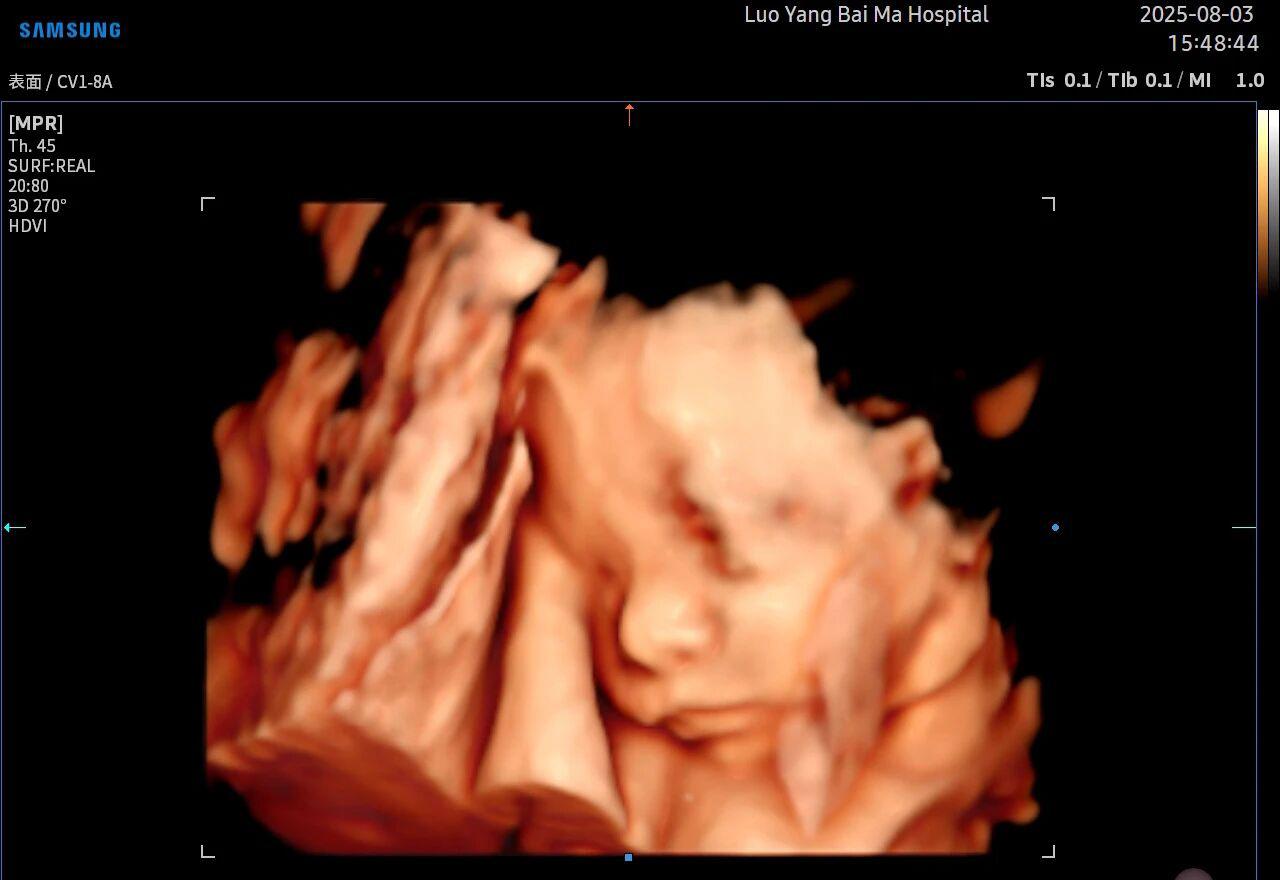

5D智能彩超拥有更高的分辨率和更强的图像处理能力,能够呈现出接近“IMAX电影画质”的细腻影像 。它采用一种被称为“水晶成像”的技术,能够穿透组织,将胎儿的骨骼、器官和组织结构以极其清晰、立体的形态展示出来。这种高清晰度对于观察胎儿微小的解剖结构细节至关重要,例如手指、脚趾、耳廓形态等,有助于医生发现一些在传统超声下不易察觉的细微异常,为排畸诊断提供了更丰富的视觉信息。

传统超声检查有时会因为胎儿体位、羊水量等因素的限制,导致某些部位观察不清。5D智能彩超技术能够实现对目标结构进行360°全方位、多切面的自由旋转观察。医生可以像“雕塑家”一样,从任意角度审视胎儿的解剖结构,尤其对于形态复杂的心脏、颅脑和脊柱等部位,这种能力可以极大弥补单一平面的局限性,帮助医生更全面地评估其发育状况。

4. 温情互动,一次充满感动的“亲子会面”

除了严谨的医学诊断价值,5D彩超也为准爸妈们带来了无与伦比的情感体验。通过高清逼真的动态影像,您可以清晰地看到宝宝的每一个细微表情和动作,仿佛他(她)就在眼前。这份提前到来的“亲密接触”,不仅能极大地缓解孕期的焦虑,更能加深家庭成员与未出世宝宝之间的情感连接,让等待的每一天都充满更具体的幸福感。